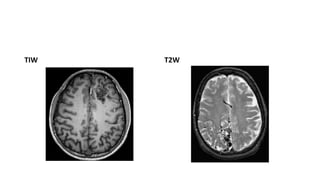

MRI

• MR findings

• T1WI

Tightly packed mass, “honeycomb” of flow voids Signal varies with flow rate, presence/age of

hemorrhage

• T2WI

Tangle of serpiginous, ‘honeycomb’ of flow voids . Little/no brain inside nidus. Some gliotic

high signal may be present

TIW T2W

• #25 T1 SHOWS HONEY COMB PATTERN OF FLOW VOIDS T2-weighed magnetic resonance image of the brain demonstrates numerous flow voids suggestive of an underlying arteriovenous malformation in the right occipital lobe.